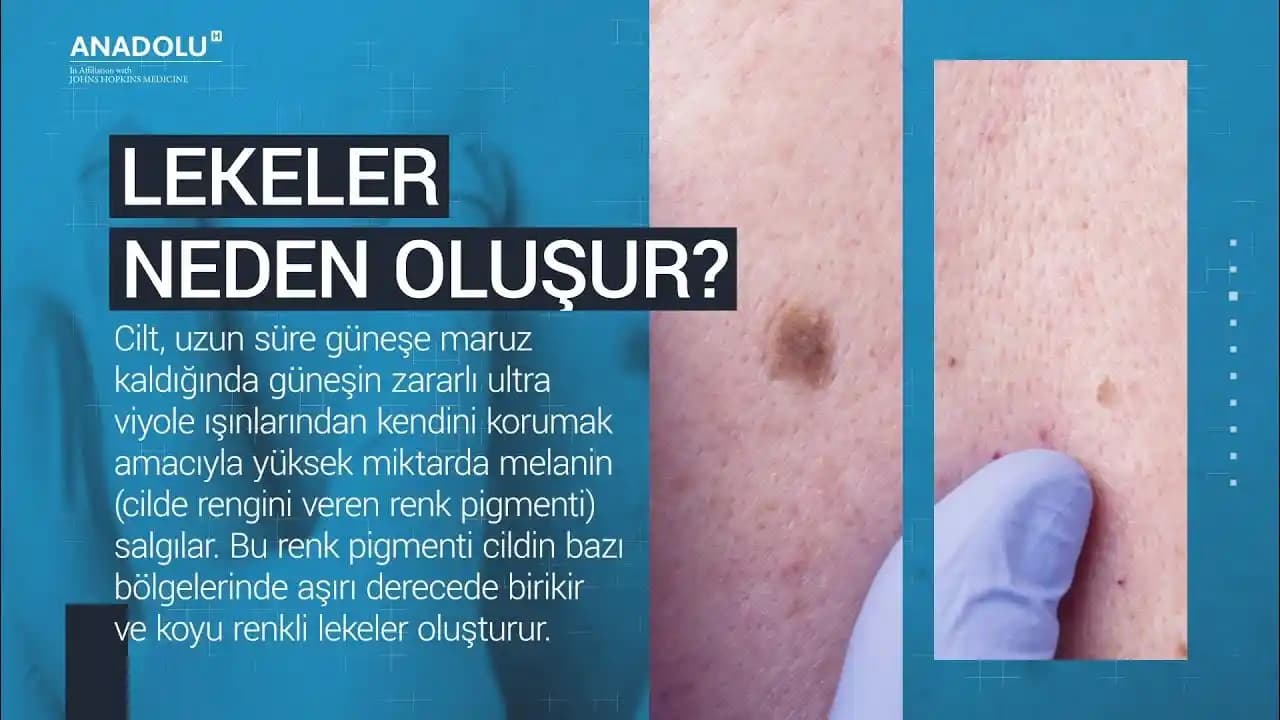

Cilt sağlığı, genel sağlığın önemli bir parçasıdır ve cilt, vücudumuzun dış dünyaya açılan penceresini temsil eder. Cildimiz, hem fiziksel hem de psikolojik açıdan sağlığımızı etkileyen birçok faktörden etkilenir. Bu nedenle, cilt bakımının önemini anlamak ve bu konuda bilgi sahibi olmak, cildimizi koruma ve sağlıklı tutma yolunda kritik bir adımdır.

Cilt sağlığı, sadece görsel estetikle sınırlı değildir; aynı zamanda yaşam tarzı, beslenme ve çevresel faktörler gibi unsurlarla da doğrudan ilişkilidir. Doğru cilt bakımı ile cildin nem dengesi sağlanabilir, yaşlanma belirtileri azaltılabilir ve cilt rahatsızlıklarından korunma şansı artırılabilir.